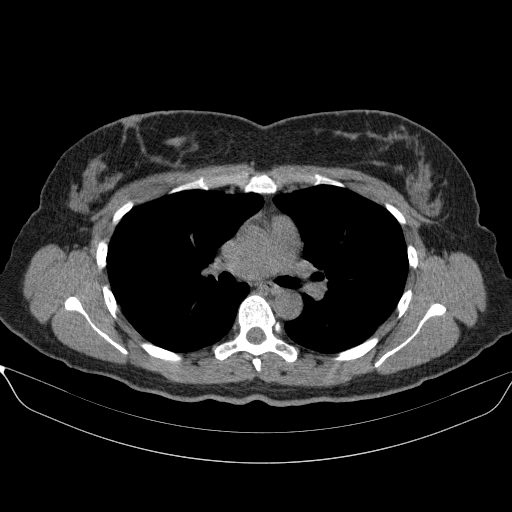

Image Grid

4Γ—3 grid: Rows show different image types (Original NATIVE, Reconstructed NATIVE, Original VENOUS, Generated VENOUS), Columns show windowing techniques (No Window, Lung Window, Mediastinum Window)

Original NATIVE CT scan (input)

No window - Raw intensity values

Reconstructed NATIVE CT scan (cycle consistency)

Original VENOUS CT scan

Generated VENOUS CT scan (A→B translation)